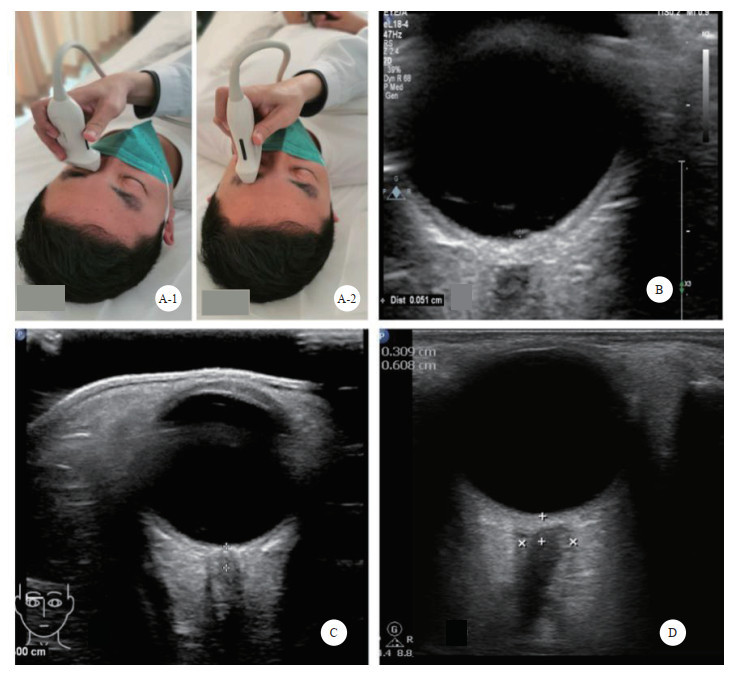

2 院前急救中不同部位伤情的超声快速诊断 2.1 颅脑超声脑外伤常伴随着颅内压(intracranial pressure, ICP)的升高,颅内压升高的三联征:头痛、呕吐和视神经盘水肿;严重者可能还伴有昏迷、意识模糊等临床表现。ICP升高是颅内并发症的早期信号,也是晚期死亡的主要原因。在紧急救治中临床单靠瞳孔或意识等某项指标来判断ICP升高情况往往不够准确[18]。超声测量视神经鞘直径(optic nerve sheath diameter, ONSD)是近几年一种新型的无创颅内压监测方法,早期判断ICP增高并及时有效干预,可明显改善患者预后。大量研究证实ICP增高是ONSD扩张的独立影响因素,且两者呈中等程度的线性相关[19-20],多数研究认为颅内压增高的ONSD的临界值为5.0~5.9 mm [21-24]。ONSD在ICP增高早期即已出现扩张,且ONSD > 5.0 mm可作为判断ICP增高的阈值,其敏感度可达94%,特异度为98%[25-26]。目前,国内外对于ONSD的阈值尚无统一标准,故对于ONSD的测量并不应视为“绝对”数字,实时动态监测更有临床意义。超声测量ONSD评估ICP升高相对较准确,且快速、便捷、可重复性好,易用在急救或特殊环境抢救时对于颅脑外伤的快速颅内压测定。

检查方法:采用高频(5.0~10.5 MHz)线阵超声探头。取仰卧位,头保持正中位,双眼睑闭合,眼球尽量固定。探头轻轻地放在闭合的眼睑上,避免过度施压。扫描切面分为横断面和矢状面。调整增益使视神经及其周围组织显示更加清晰。通常选择在眼球后3 mm的位置测量ONSD,测量时与视神经鞘的长轴垂直[27](图 2)。

|

| A: 视神经鞘探查体位及探头位置,A-1横切, A-2纵切;B:视盘的测量;C:视神经鞘的测量;D:颅高压时,ONSD水肿、增厚 图 2 超声测量视神经鞘直径 |

|

|

【推荐意见2】航天员返回后出现脑外伤,可通过超声对视神经鞘直径、视盘突起度及脑中线情况进行颅内压的评估。根据航天员标准的身高体重,可将ONSD > 5.0 mm或视盘突起度 > 0.5 mm,作为阈值,并做好动态监测。